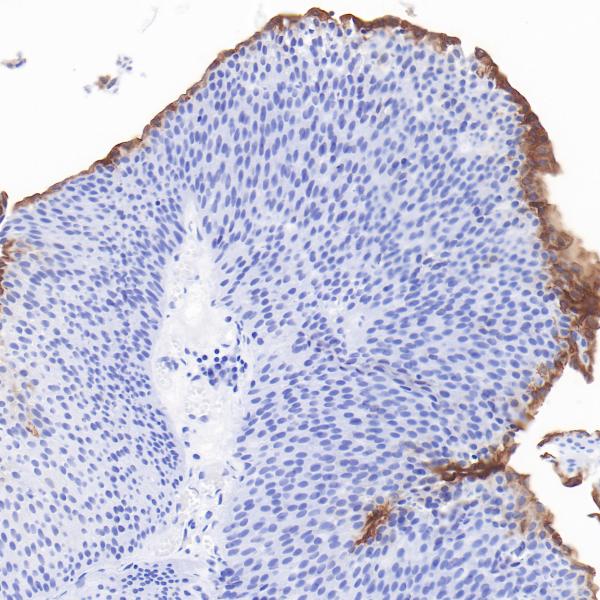

Uroplakin 1a

BP6293

Uroplakin 1b (UPK1B)

BP6310

Uroplakin II

BP6308

Uroplakin III

BP6199